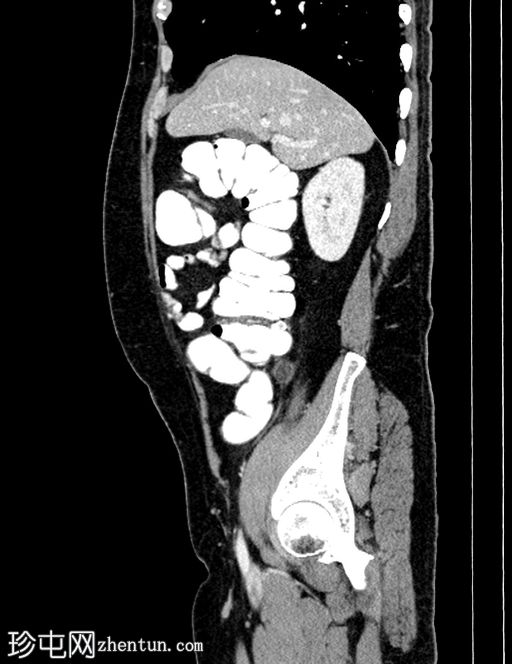

轴位增强扫描

门静脉期

门静脉期,可见一持续存在的脂肪密度影,周围环绕高密度环;周围脂肪条索状改变,无脓肿形成,邻近结肠无憩室,盲肠壁正常。无阑尾炎,无淋巴结肿大,无游离气体或液体。